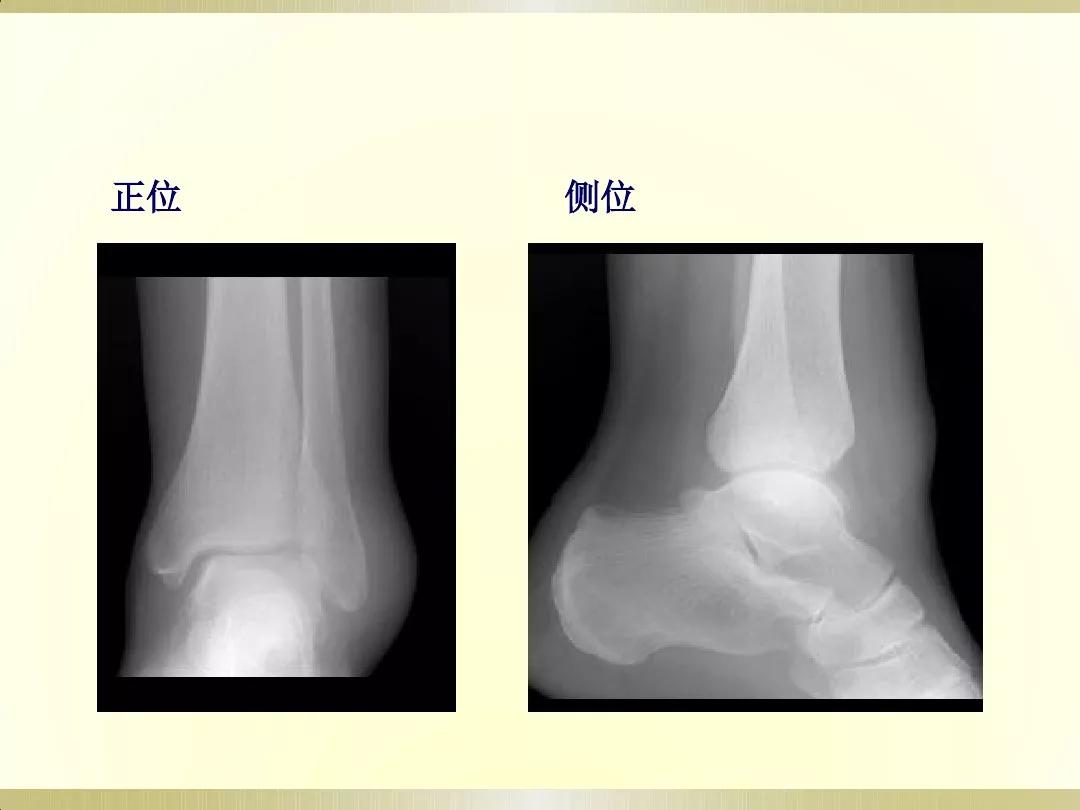

X线摄片就是通过让一种有能量的电磁波,即X射线透射过身体不同组织结构,在胶片上形成明暗或黑白对比不同的影像,被称为X线摄片。

医生可以通过X射线检查来识别各种组织,并根据阴影的形态和浓淡变化来分析其是否属于正常。这很像我们日常所说的拍照片,出来的图像是平面的。

检查部位:X线可以检查身体的许多部位。通常用于检查胸部(大致了解情况)、骨骼、肌肉或脏器,以及发现体内的气体,也可探查金属物体。